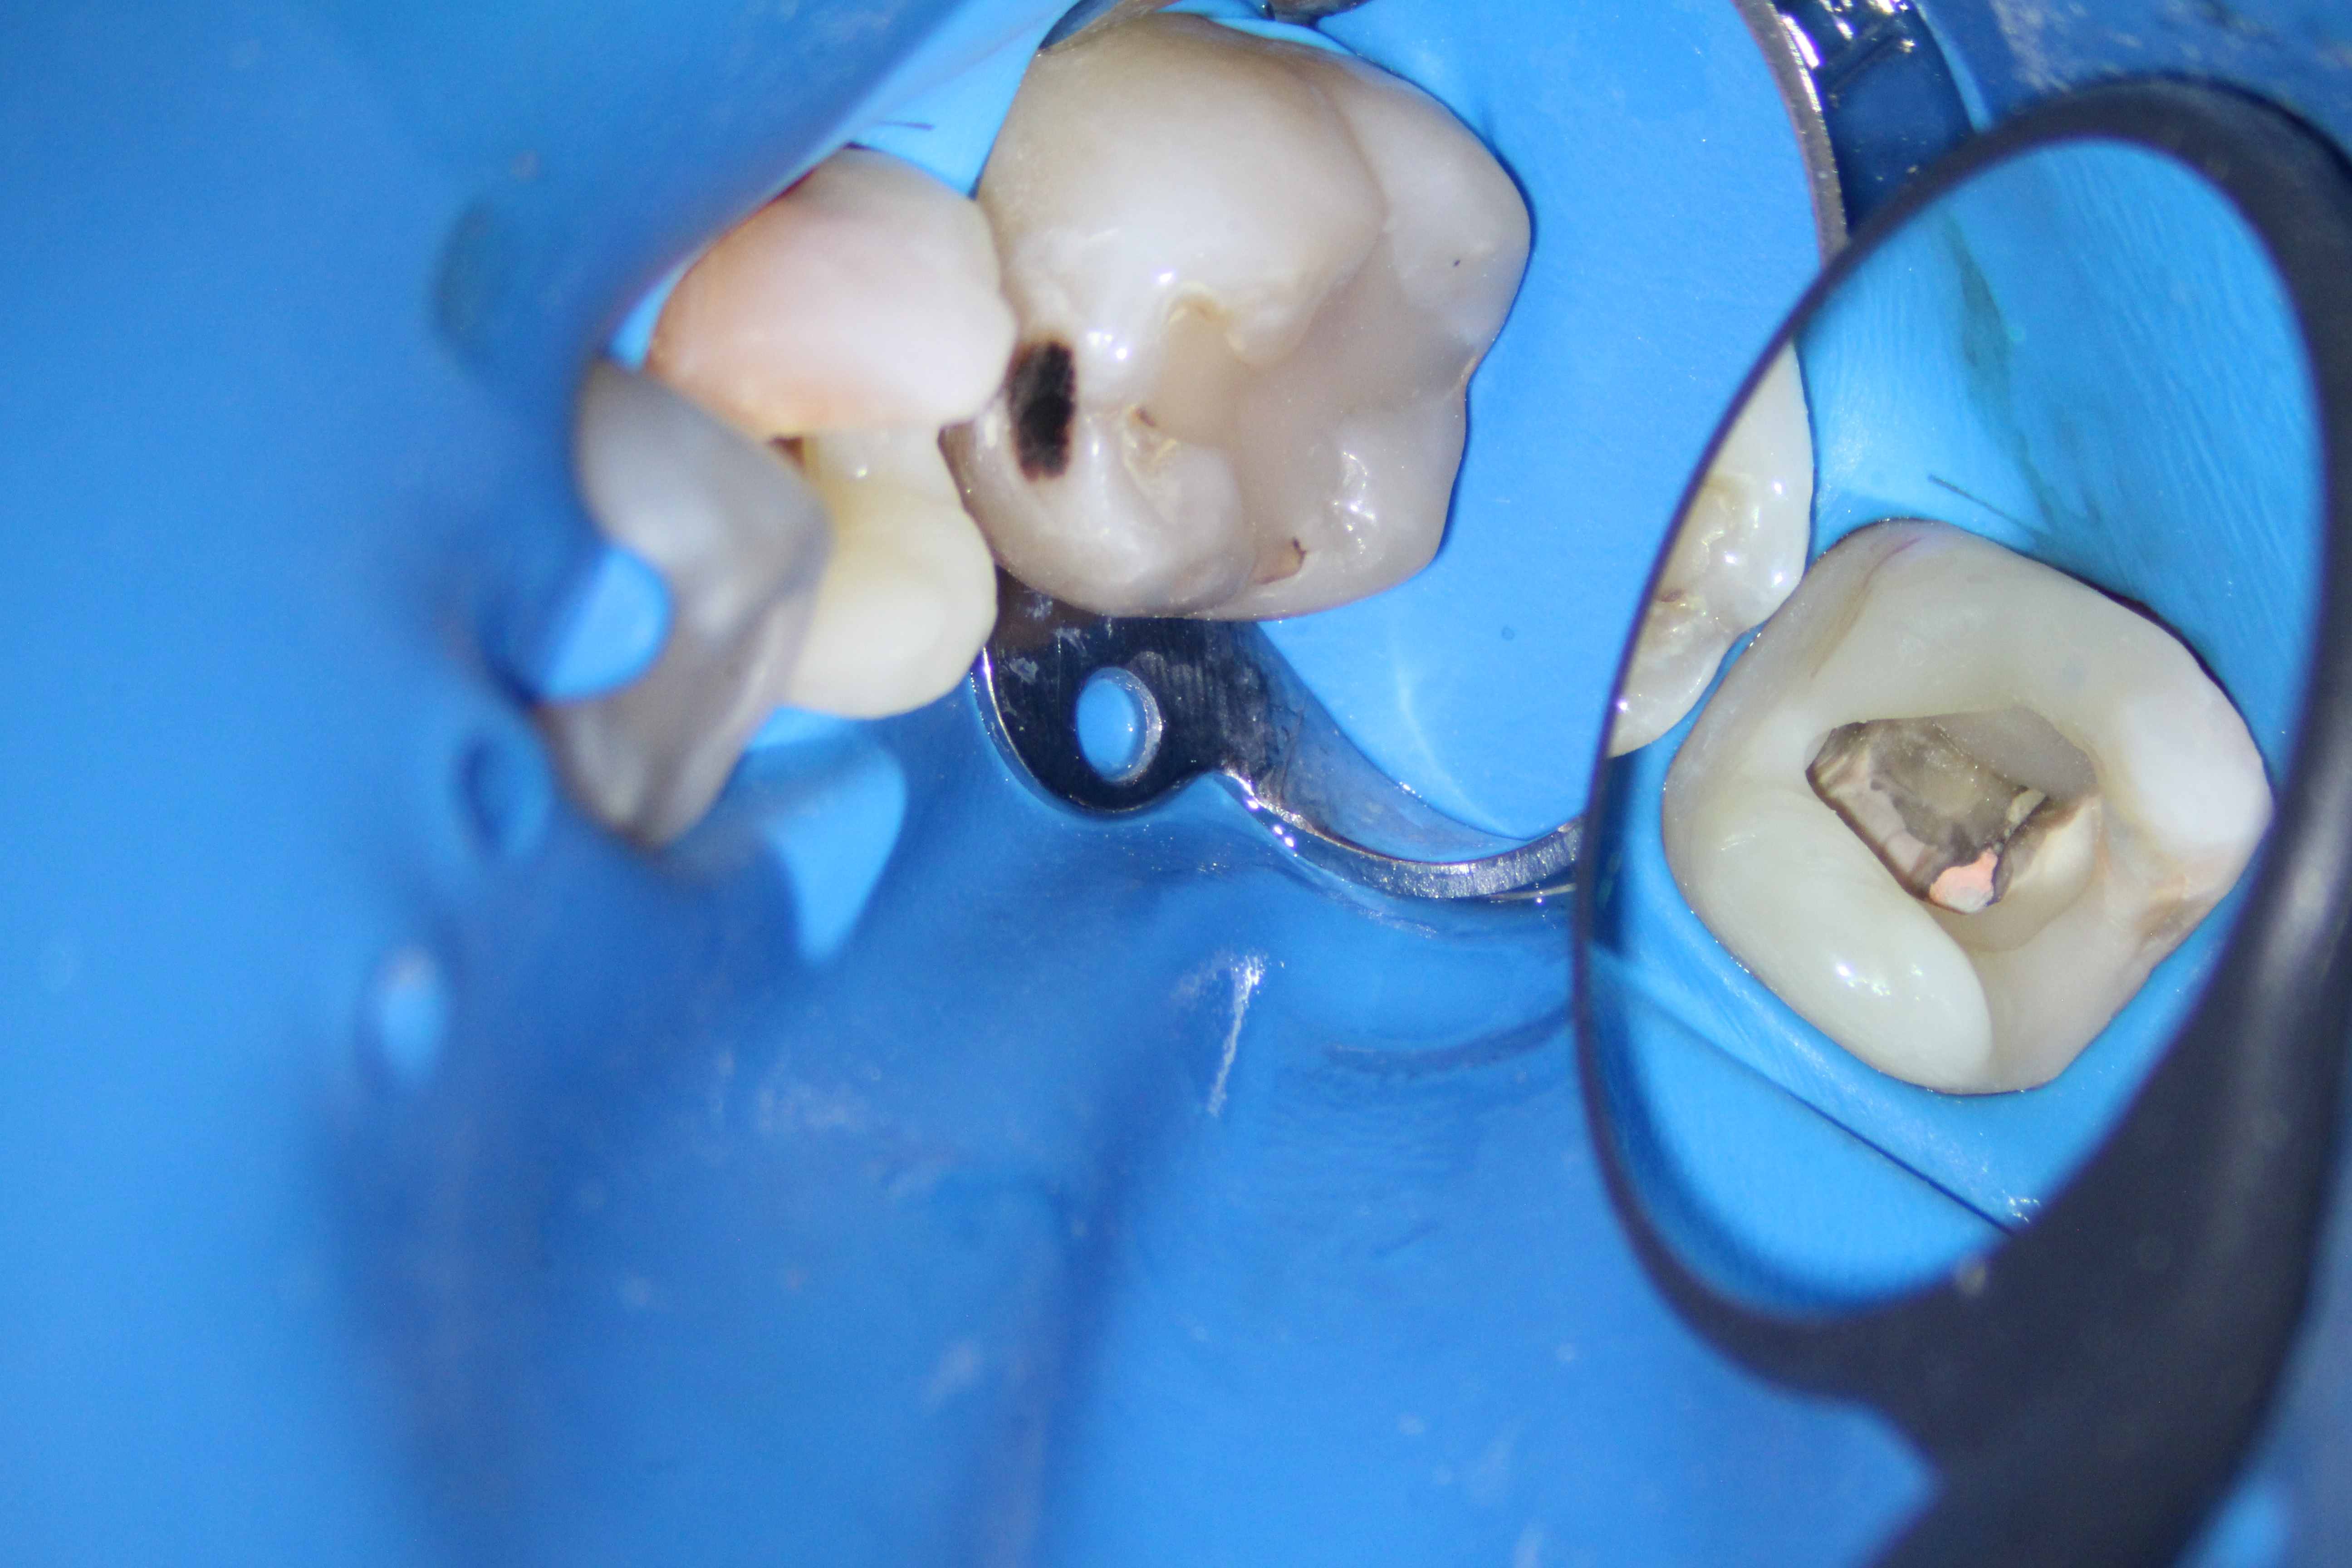

A glimpse at the process...

1

2

3

4

5